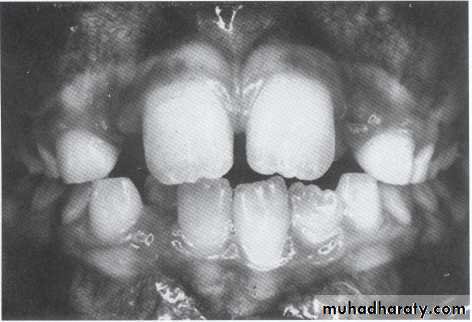

1- Maxillary – mandibular alveolar protrusion.UNIVERSITY OF MOSUL

COLLEGE OF DENTISTRY2- One permanent mandibular lateral incisor block out lingually and midline discrepancy.

3- Premature exfoliation of one primary mandibular canine with result midline discrepancy.

4- One mandibular permanent lateral incisor block out labially and midline discrepancy.5- Bilateral exfoliation of primary mandibular canine.